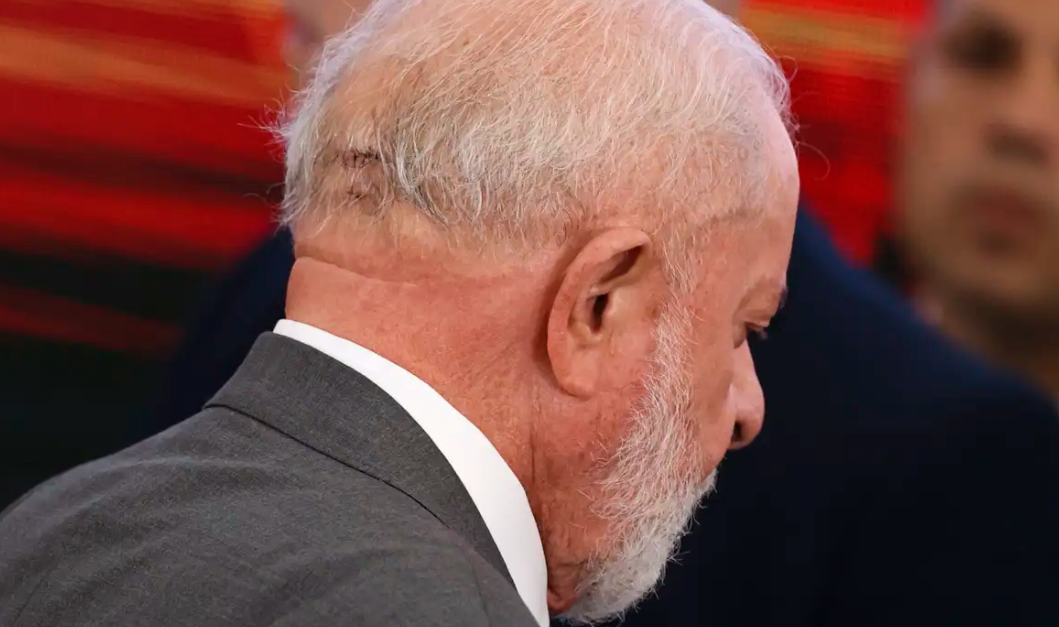

Caso do Lula: Neurologista bomba alerta se hematoma subdural crônico é na boa ou não?

Médico do Sírio-Libanês tira a real sobre o tal hematoma subdural crônico e dá aquele toque sobre o cuidado pós-queda em vovôs e vovós! O neurologista Tarso Adoni, do Hospital Sírio-Libanês, mostra que os riscos de quedas em idosos não são brincadeira. O cara explicou que o tal hematoma subdural